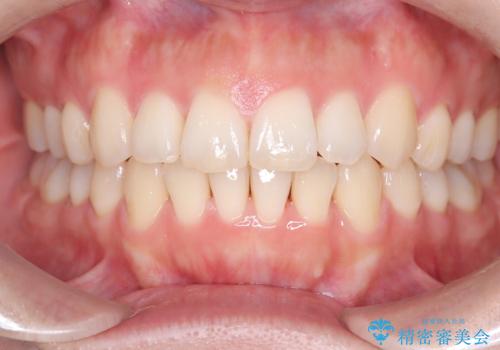

【インビザライン】前歯の凸凹を治したい

- 前歯の凸凹を主訴に来院されました。

インビザラインにて臼歯部の遠心移動を行いながら、できるだけ前歯が出ないように気を付けて治療を行っています。

遠心移動を行う必要があったので、患者様には顎間ゴムを使用していただきました。